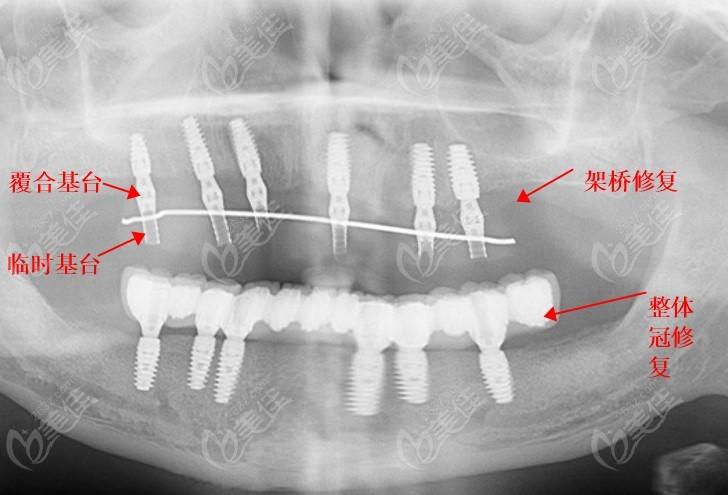

种植牙半口桥架的舒适度也是它的一大优势。它使用的是高科技材料,不仅质地轻巧,而且结实耐用,不会对口腔造成过多的负担。种植牙半口桥架的基底是由轻质高强度金属或纯钛制成,更加人性化的设计,能够最大程度地减少对口腔的刺激,让人感到非常舒适。

种植牙半口桥架的耐用度也是它的一大优势。它使用的是高质量的材料,能够承受较大的压力,不易损坏。而且,种植牙半口桥架的修复效果非常好,能够长时间保持良好的状态。

与传统的义齿相比,种植牙半口桥架的耐用度要高得多。它的寿命能够达到10年以上,对于年轻人而言,甚至可以使用一生。这种优越的耐用度,不仅让人们省去了不断更换义齿的麻烦,同时也节省了不少费用。